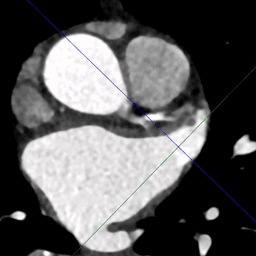

O Amplifier transforma a angiotomografia em uma reconstrução fotorrealista e imersiva do anel aórtico, LVOT, óstios coronarianos ou apêndice atrial esquerdo — pronta para simulação em realidade virtual.

Com uma biblioteca curada de próteses para TAVI e oclusores para LAAC, em escala real, é possível inserir o dispositivo desejado, ajustar profundidade, rotação e flare, e visualizar métricas em tempo real como tensão anular, vazamento paravalvar e fluxo residual.

Ferramentas com linha central e sobreposições em cores ajudam a avaliar a curvatura do cateter, o ângulo trans-septal e a distância até estruturas críticas. Ao ensaiar o procedimento completo em um modelo específico do paciente, as equipes reduzem fluoroscopia, minimizam contraste e entram no laboratório com confiança total.